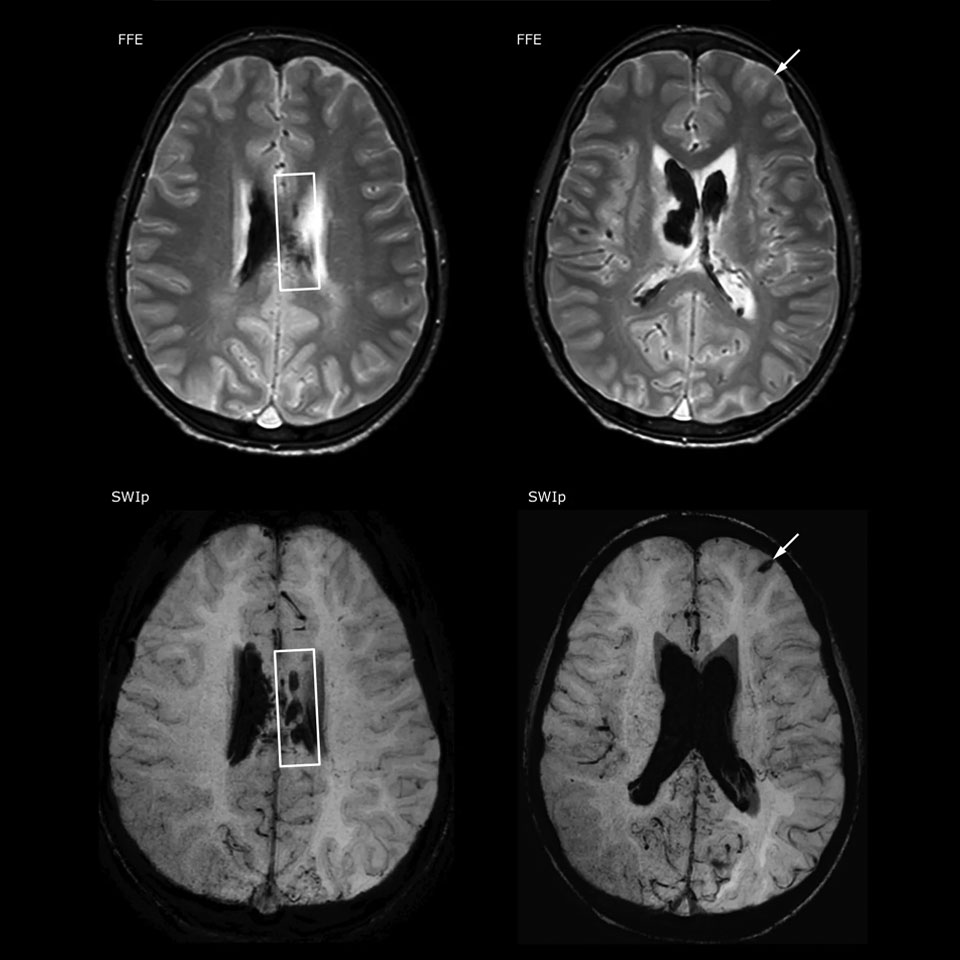

The value of susceptibility weighted imaging in visualizing brain injury is well documented. The Philips multi-echo SWIp technique provides fast susceptibility weighted imaging with enhanced susceptibility contrast and high resolution.

“SWIp helps us identify blood or blood products, calcification, and diseases that affect the vascular system,” says Dr. Miller. “In children with traumatic brain injuries, it highlights areas that are injured, better than some of the previous techniques that we were using. These children often have micro-injuries that cause small amounts of blood or tissue damage. Adding SWIp helps us to better characterize the extent and nature of the injury. Having characterized an injury to the extent of what’s possible supports our diagnostic confidence.”

“I would definitely recommend other users to implement SWIp. We initially added the SWIp sequence following a lot of support for its utility in the literature. Then we directly compared SWIp to the 2D gradient echo sequences that we were using. After a good amount of clinical experience in seeing its benefits, we were confident to replace the old sequences with SWIp. It gives us a better assessment of the physiological processes of the brain that were less apparent on our previous imaging sequences,” says Dr. Miller. “SWIp is now a routine sequence for imaging traumatic brain injury patients at PCH, and it’s episodically added for patients who have intracranial vascular abnormalities.”